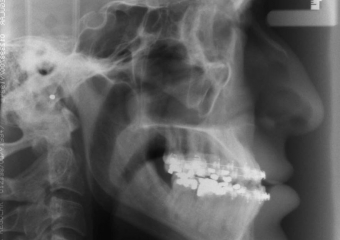

Telerradiografia inicial